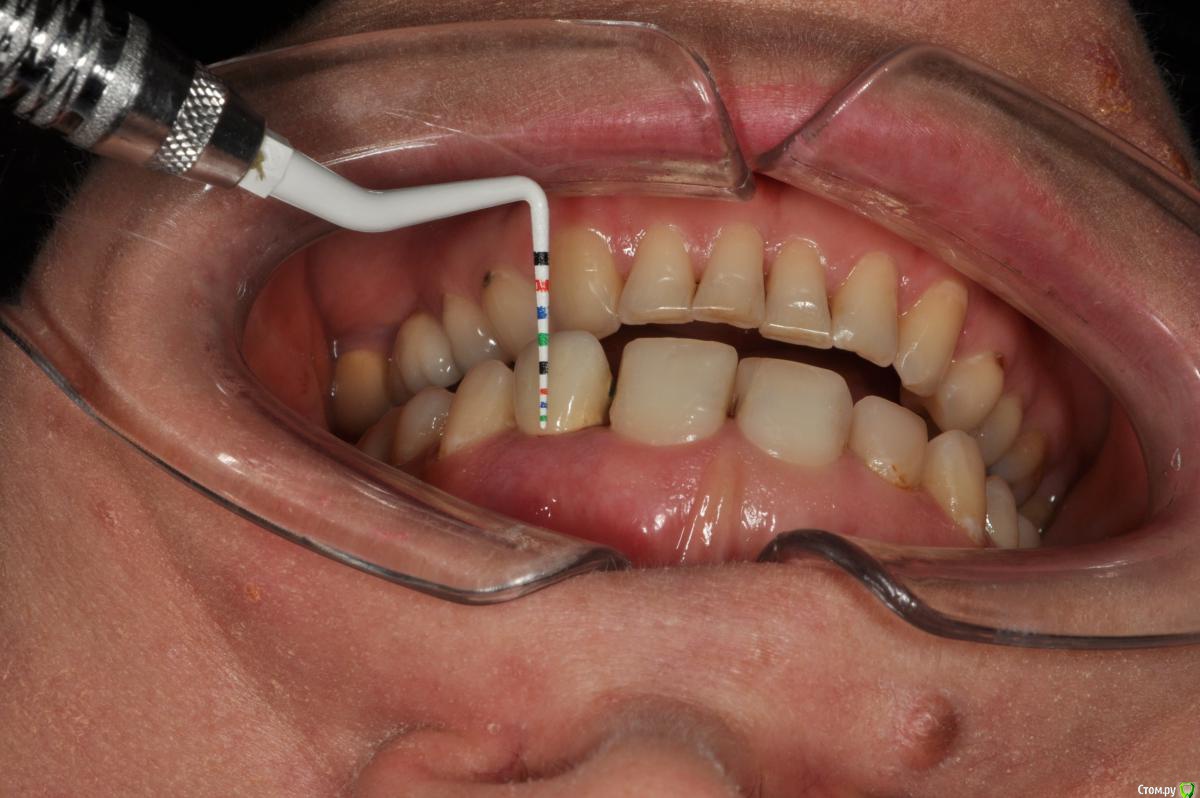

Пациентка 37 лет, не курит, соматически здорова. Частое выпадение ЛШКВ с коронкой. Диагностирована  фрактура вестибулярной стенки кореня зуба 22. Линия улыбки высокая. Биотип толстый.  Отсутствие вестибулярной пластинки, карман 8мм без ексудата.  Латеротрузия через 22.